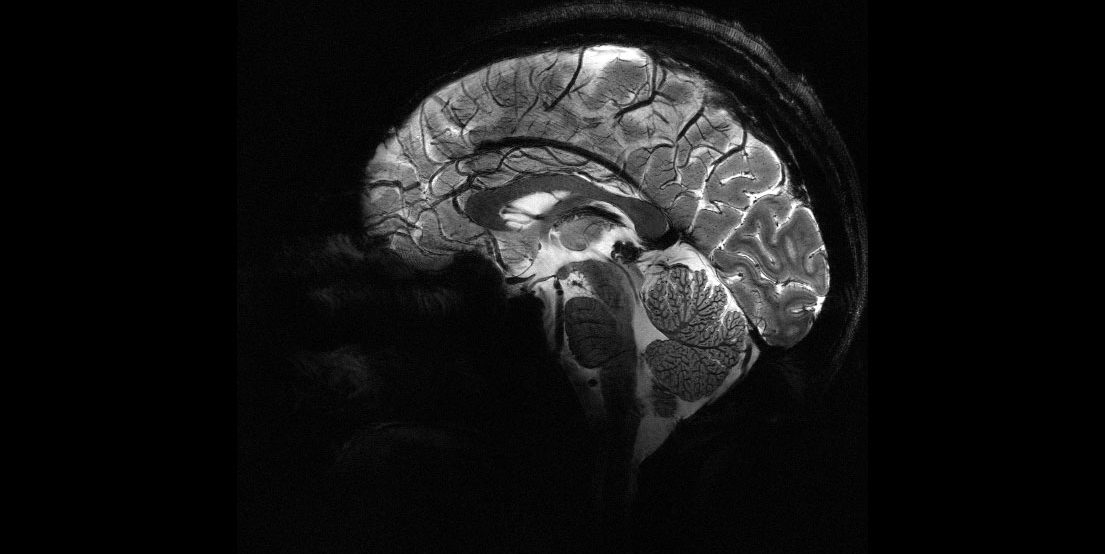

Наймогутніший у світі МРТ створив перші знімки людського мозку

Мозок людини на Iseult Magneton 11,7 T МРТ. Фото: CEA

Варто зауважити, що впродовж кількох років вчені будуть тестувати Iseult на добровольцях. Звичайні пацієнти не зможуть використовувати апарат для клінічної діагностики.

Дослідники сподіваються, що потужність сканера зможе пролити світло на механізми нейродегенеративних захворювань, таких як хвороба Паркінсона чи Альцгеймера, або психологічних станів, таких як депресія чи шизофренія.